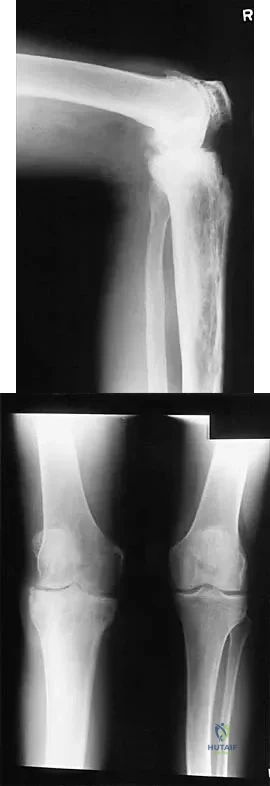

Question 27

A previously asymptomatic 12-year-old girl sustained a direct blow to the right lateral knee from a baseball bat. Examination reveals an area of ecchymosis and tenderness over the lateral thigh. The patient can walk without pain, but range of motion of the knee causes discomfort. Plain radiographs of the knee are shown in Figures 11a and 11b. To address the bone lesion, management should consist of

Explanation